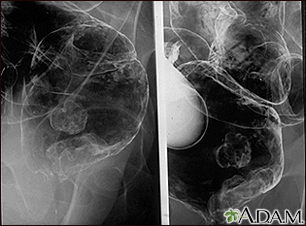

Rectal cancer - x-ray